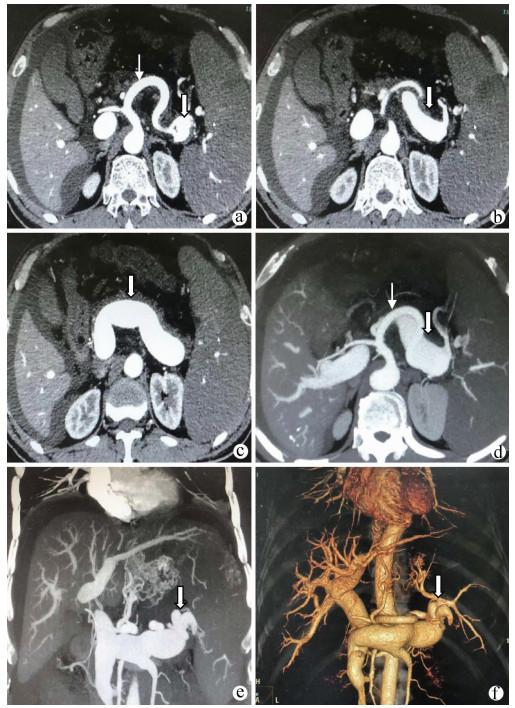

A case of splenic arteriovenous fistula with abdominal pain and gastrointestinal bleeding as the first symptoms

Yuanyuan CAI, Zhongwen WU, Juan LU

2021, 37(5): 1186-1188. DOI: 10.3969/j.issn.1001-5256.2021.05.043

Abstract(1061) HTML (301) PDF (2876KB)(57)

Abstract: